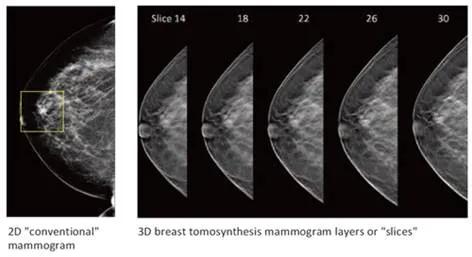

2D vs 3D mammography

3D mammography, also known as digital breast tomosynthesis, takes multiple images (or slices) from the breast to create a 3D image. It can take more time to diagnose digital breast tomosynthesis studies because radiologists must scroll or cine through many images. At the same time, it is more challenging to clearly detect microcalcifications in moving images. Special mammography displays can counter these challenges, ensuring crisp and in-focus moving images with no blurring.